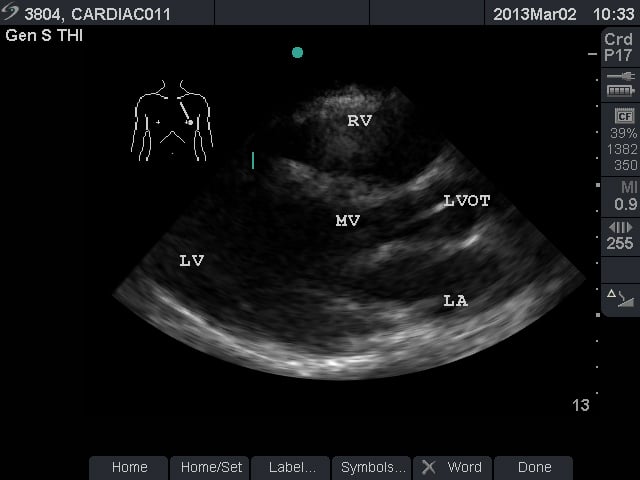

Video 1. Normal Subxiphoid View - Parasternal Long Axis View: This view captures the flow of blood through the left side of the heart. The apex is to the left of the screen. The mitral valve leaflets are seen and often chordae tendinae connecting them to papillary muscles. Two cusps of the aortic valve (usually the non-coronary and right coronary cusp) are seen. The left ventricular outflow tract (LVOT) is the term for the aortic root and proximal ascending aorta. A portion of the right ventricle is seen in the near field.

- Figure 2. Parasternal long axis view. RV = Right ventricle. LV = left ventricle. MV = mitral valve. LVOT = left ventricular outflow tract. LA = left atrium